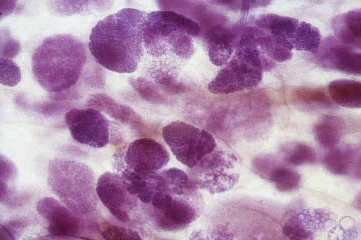

Der Stamm des Baums endet in der Brustwarze, seine Äste und Zweige entsprechen den Milchgängen, und die Blätter bilden die Milchdrüsenläppchen. Die 'Blätter' sind allerdings nicht flach, sondern sehen eher wie Himbeeren mit einem kurzen Stiel aus - hier eine Sicht durch das Mikroskop:

Der Stamm des Baums endet in der Brustwarze, seine Äste und Zweige entsprechen den Milchgängen, und die Blätter bilden die Milchdrüsenläppchen. Die 'Blätter' sind allerdings nicht flach, sondern sehen eher wie Himbeeren mit einem kurzen Stiel aus - hier eine Sicht durch das Mikroskop:

Mit freundlicher Genehmigung von Prof. László Tabár